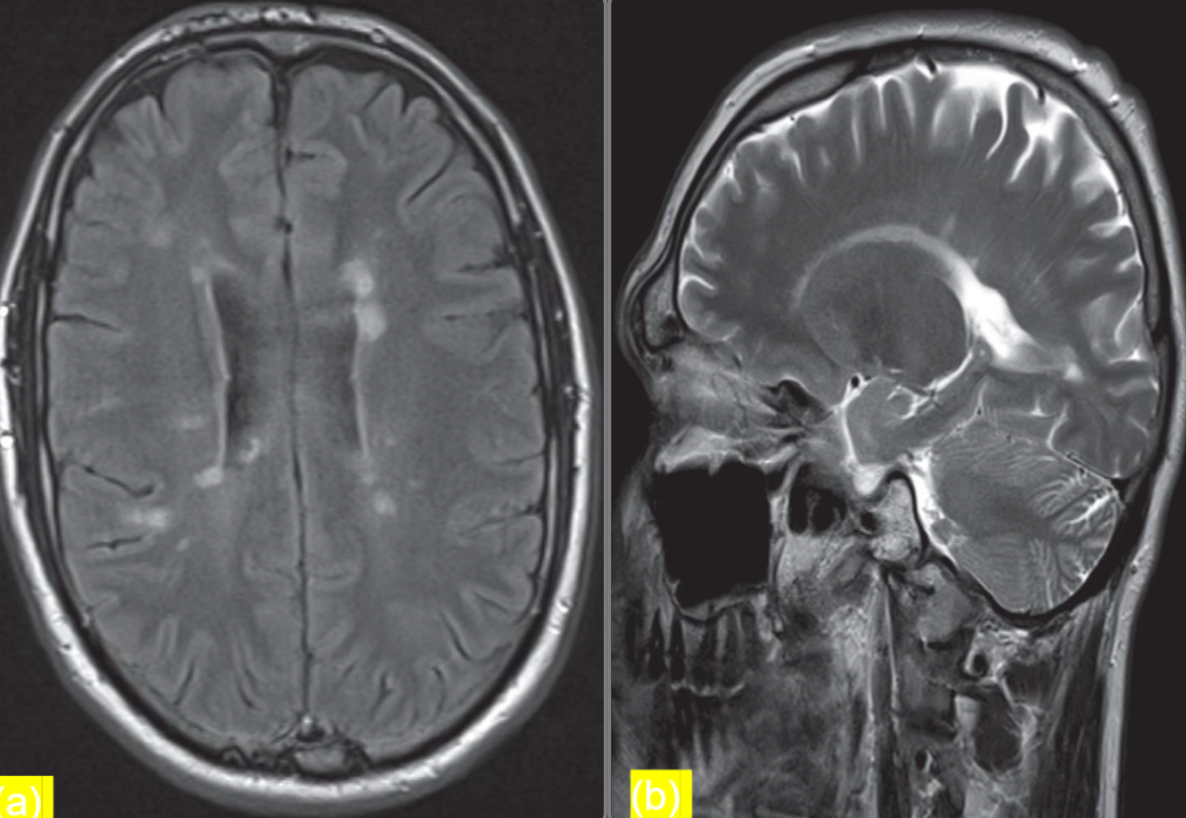

Patients presents with optic neuritis

(a) Axial FLAIR sequence at the level of the lateral ventricles

- shows periventricular areas of linear and ovoid hyperintense

- signal orientated perpendicular to the body of the right lateral ventricle. This feature is known as Dawson fingers and is

- strongly associated with multiple sclerosis.

(b) Parasagittal T2-weighted MRI

- shows plaques of demyelination as high signal in the white matter, particularly along the

- margins of the lateral ventricles

Modality MRI Findings Plaques of demyelination, dawson fingers Diagnosis multiple sclerosis